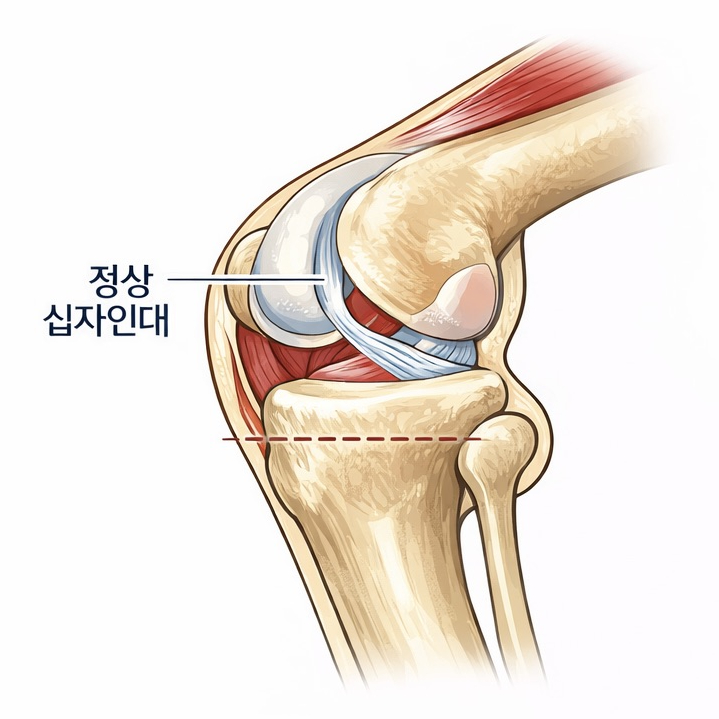

슬개골 탈구 수술은 단순히 빠진 뼈를 제자리로 돌려놓는 수술이 아닙니다.

무릎 관절의 정렬, 뼈의 구조, 연부조직 상태를 종합적으로 판단해 아이에게 맞는 수술 계획이 필요합니다.

슬개골 탈구 수술은 정확한 진단과 수술 환경이 결과를 좌우합니다.

수술 전·후 방사선 검사를 통해 관절 정렬과 수술 결과를 객관적으로 평가합니다.